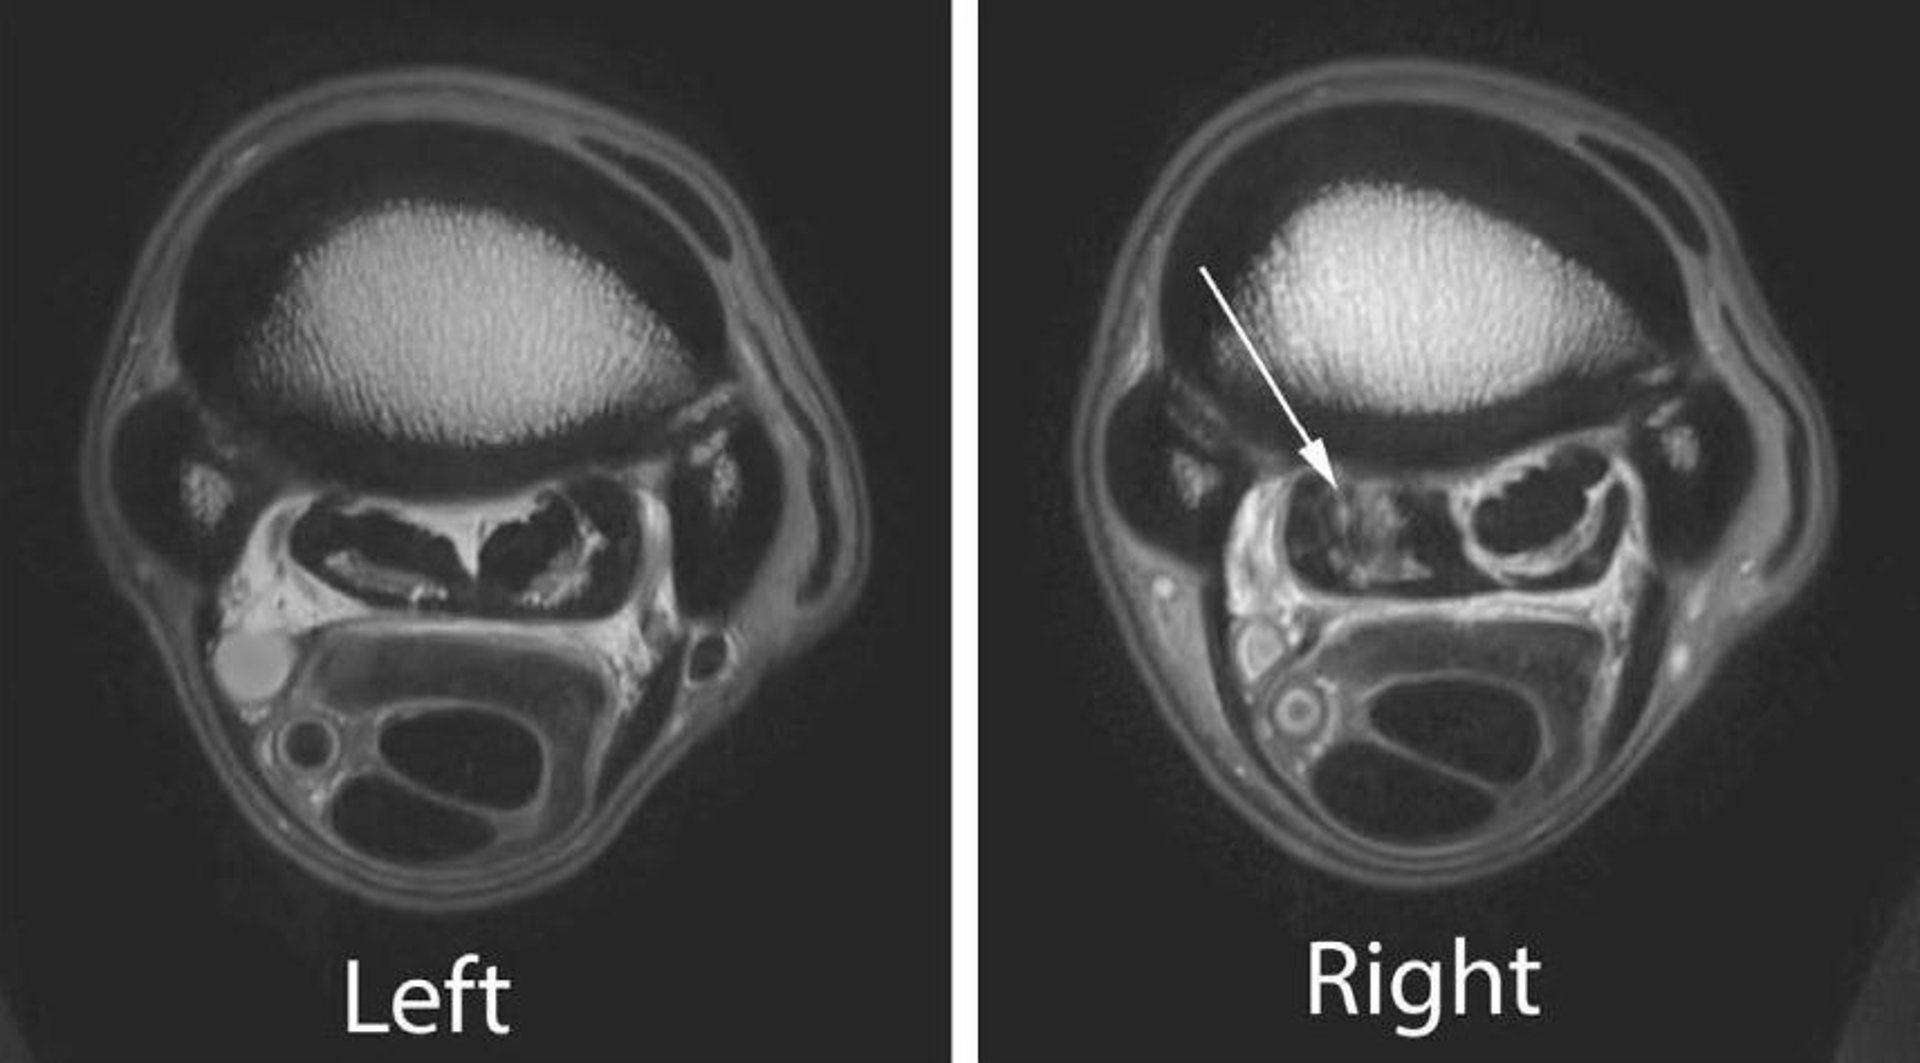

Nuclear scintigraphy can help detect concurrent or primary osseous injury at the proximal suspensory attachment. MRI is also extremely useful to detect subtle changes in the proximal suspensory ligament that might not be visible or conclusive with ultrasonography (see ), and MRI allows concurrent examination of bony structures.

Transverse magnetic resonance images of the proximal metacarpal region in a horse, showing the irregularity and increased signal in the medial aspect of the right front proximal suspensory ligament (arrow). The left side is normal.

Courtesy of Dr. Matthew T. Brokken.